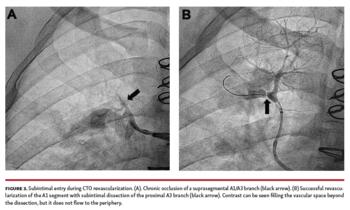

Of the 15 identified CTOs, 8 were located at the segmental level, 5 subsegmental, and 2 suprasegmental. Procedural success was achieved in 13 out of 21 interventions. Ten out of 13 lesions with a successful intervention required only 1 intervention to establish vessel patency. One lesion required 2 separate interventions and 2 lesions required 3 separate interventions in order to achieve success. Two lesions were not successfully revascularized on any attempt. Revascularization was attempted once for 1 of these lesions and twice in the other lesion. Of the 13 successful interventions, 7 lesions were wired from true lumen to true lumen using a Pilot 200 (Abbott Cardiovascular) (n = 4), Astato 20 (Asahi Intecc) (n = 2), or Sion guidewire (Asahi Intecc) (n = 1). In the remaining 6 lesions, the guidewire was recognized to be subintimal well beyond the occlusive cap. Re-establishment of intraluminal wire position was achieved in 3 interventions using subintimal tracking and re-entry (STAR) technique4 with Pilot 200 (n = 2) and Suoh wires (Asahi Intecc) (n = 1) wires. Luminal re-entry was achieved via antegrade dissection and re-entry (ADR) technique with a Stingray balloon (Boston Scientific) in 2 cases (Figure 2) and with direct wire re-entry using a Mongo wire (Asahi Intecc) in 1 case. Follow-up angiography was performed on 7 of the revascularized CTO lesions at a subsequent intervention at least 1 week post successful intervention. All 7 reimaged lesions were found to be widely patent. Follow-up angiography during subsequent sessions has not yet been performed on the remaining 6 lesions.

One clear challenge for CTO intervention is interpretation of distal lesion pathology. For example, early interventions occasionally resulted in an angiographic pattern of contrast distal to the lesion within a vascular space, but without distal flow into the capillary bed or pulmonary veins. We initially interpreted this as heavy thrombotic disease beyond the proximal occlusion; however, attempts at distal balloon angioplasty never resulted in restoration of forward flow into the periphery or pulmonary venous return when this initial pattern was seen. It was only after repeated interventions that we recognized this as the angiographic pattern of subintimal dissection within the PAs (Figure 3). As our understanding of subintimal vessel anatomy evolved and our success rate improved, we found that re-entry into the PA lumen just beyond the occlusive cap with either STAR or Stingray balloon technique resulted in significant vessel recruitment. In hindsight, the vast majority of our failed interventions were due to misinterpretation of subintimal dissection as heavy thrombotic burden, offering the possibility for higher success rates during the initial intervention as we improve our ability to work within this space.